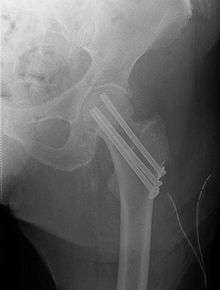

Fracture supported by dynamic hip screw

An intertrochanteric fracture, below the neck of the femur, has a good chance of healing. Treatment involves stabilizing the fracture with a lag screw and plate device to hold the two fragments in position. A large screw is inserted into the femoral head, crossing through the fracture; the plate runs down the shaft of the femur, with smaller screws securing it in place.

The fracture typically takes 3–6 months to heal. As it is only common in elderly, removal of the dynamic hip screw is usually not recommended to avoid unnecessary risk of second operation and the increased risk of re-fracture after implant removal. The most common cause for hip fractures in the elderly is osteoporosis; if this is the case, treatment of the osteoporosis can well reduce the risk of further fracture. Only young patients tend to consider having it removed; the implant may function as a stress riser, increasing the risk of a break if another accident occurs.